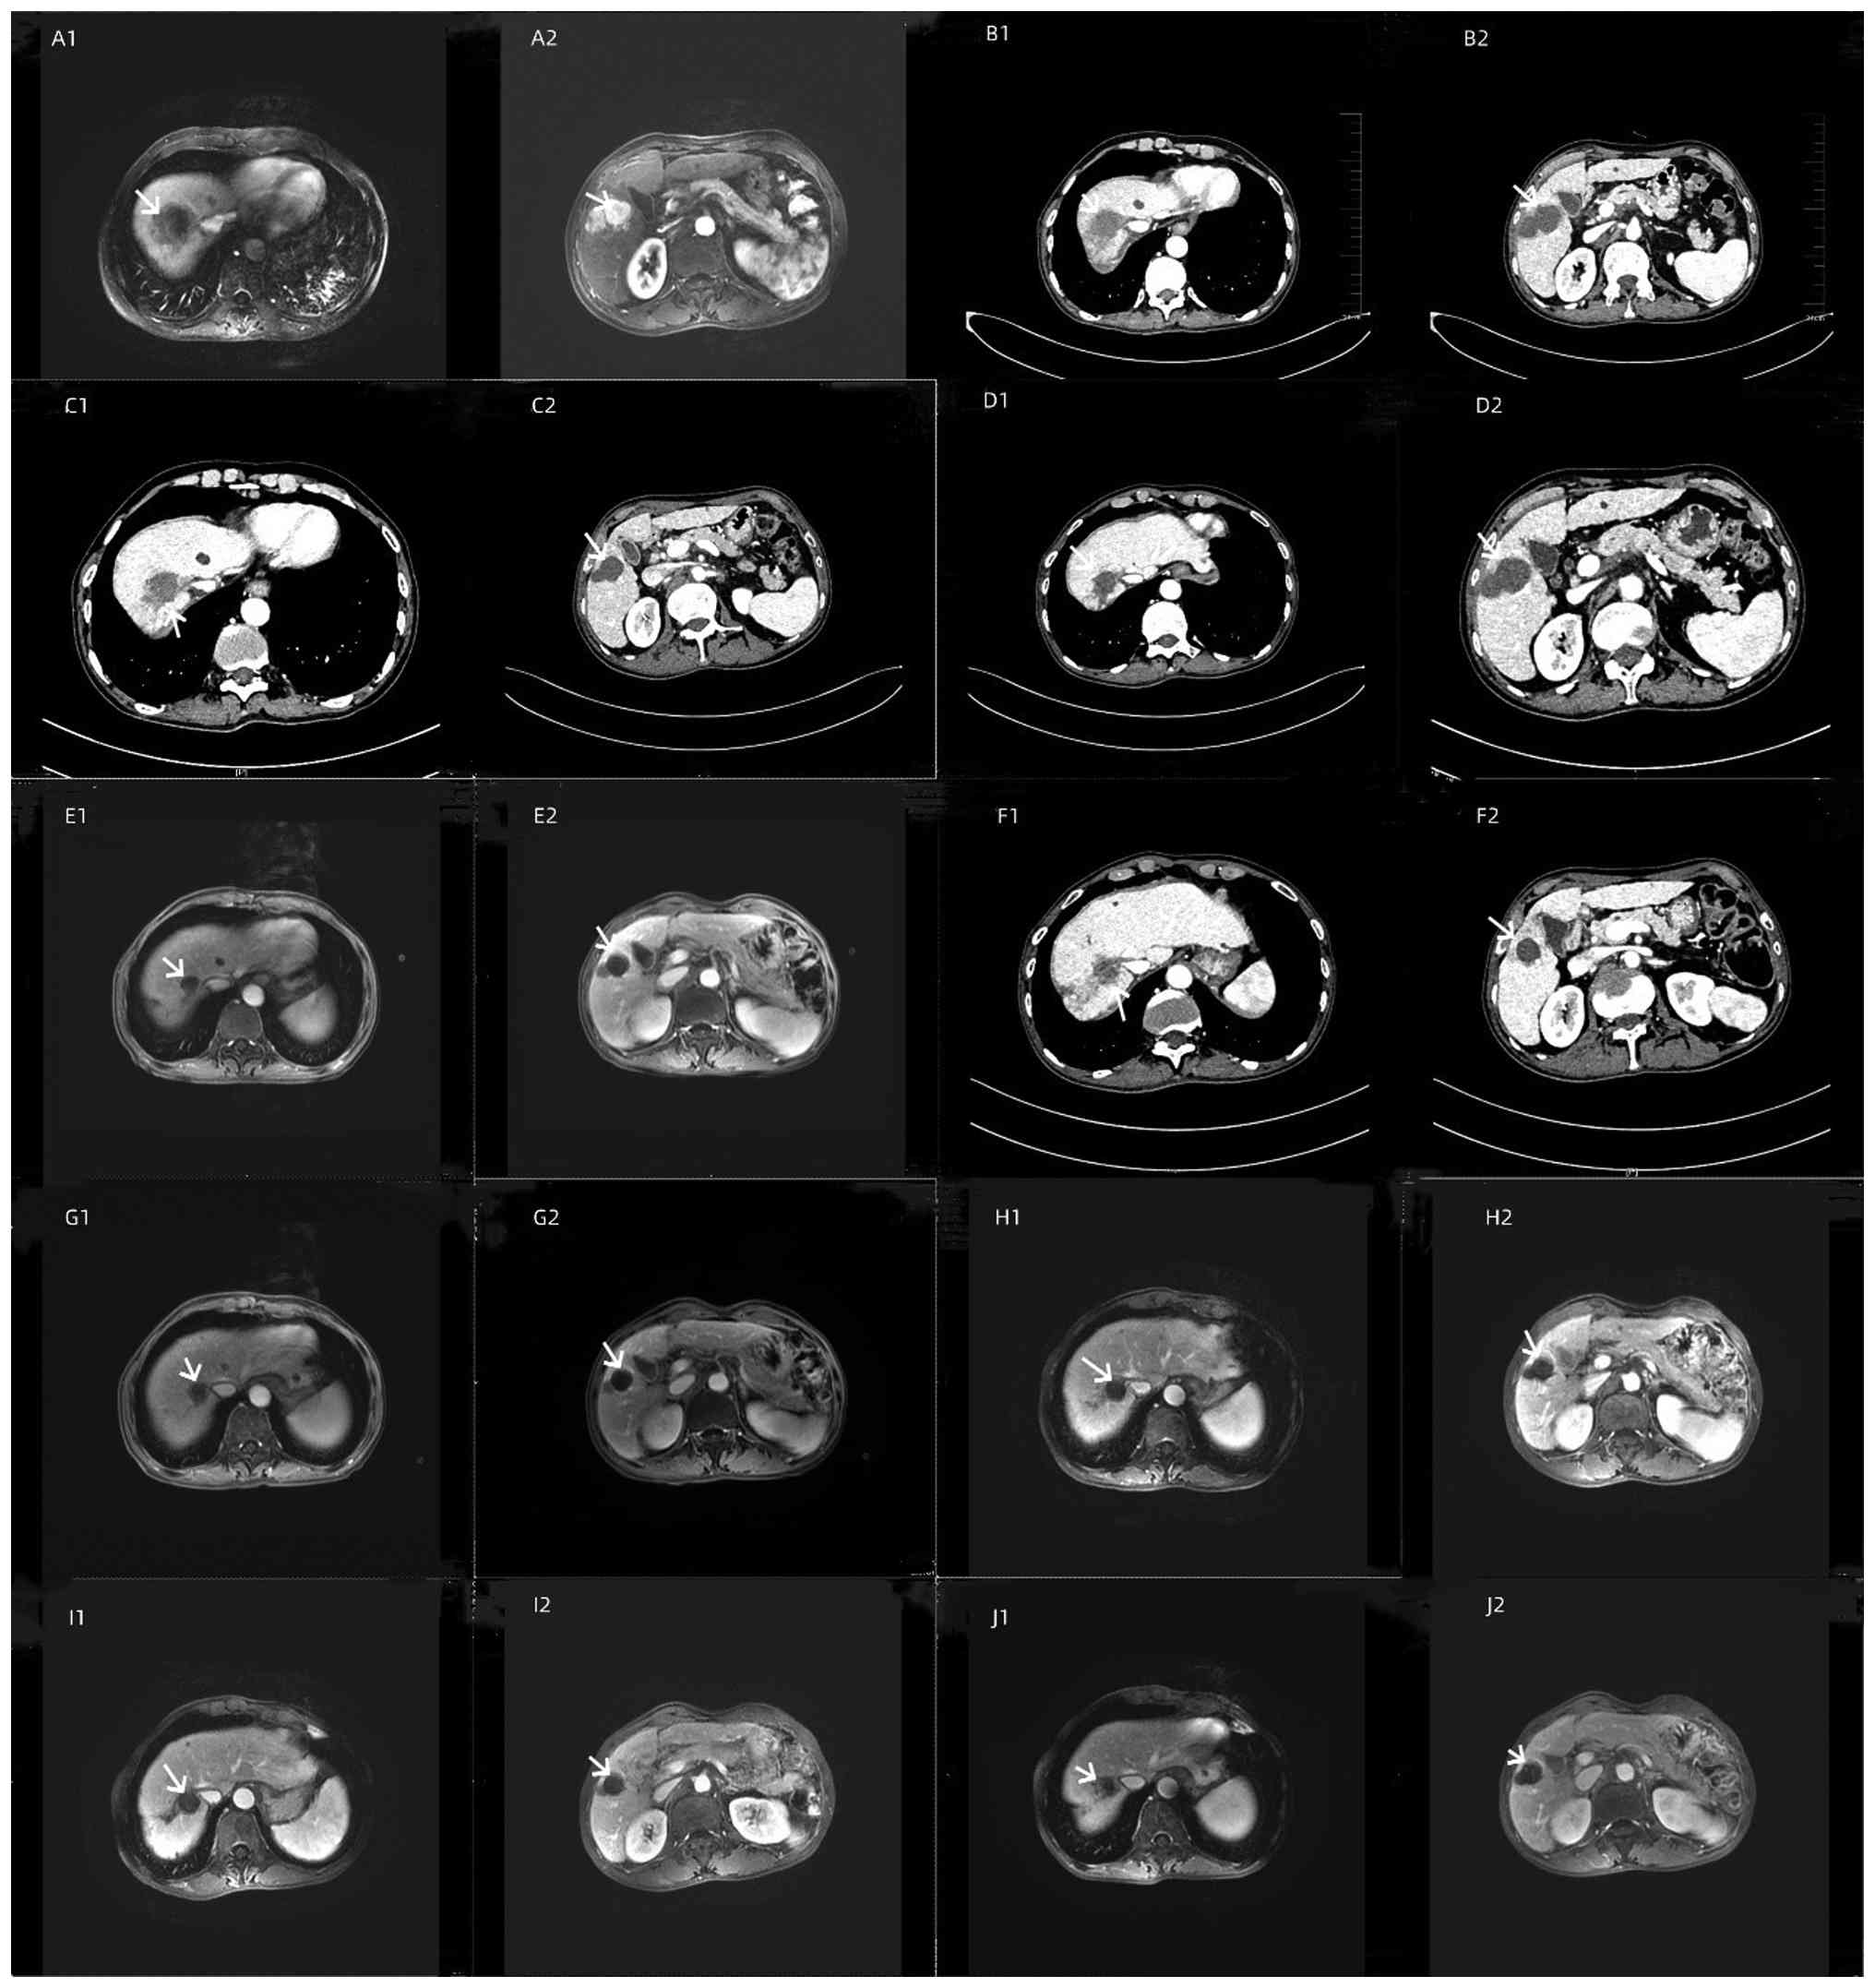

To date, the patient has undergone seven sessions of TACE and eight sessions of combined targeted immunotherapy, and the patient's condition is stable (Table I). Following the initiation of combined therapy, the tumor size gradually decreased and stabilized on serial imaging assessments performed between June 2022 and August 2024 (Fig. 7); liver function has remained stable (Fig. 8), and tumor marker levels have gradually decreased and stabilized (Fig. 9). As of August 2024, no significant adverse reactions have been observed. Quality of life has significantly improved and the patient is still undergoing regular follow-up.

Case 2: Serial imaging demonstrating

tumor response to combination therapy. Paired axial images show

changes in the target lesions in (A1-J1) segment S7-8 (left column)

and (A2-J2) segment S5-6 (right column) over time. White arrows in

all panels indicate the primary tumors. (A1 and A2) Baseline

imaging prior to treatment (July 2022); (B1 and B2) Imaging

following the first TACE session (September 2022); (C1 and C2)

Imaging following the second TACE session (October 2022); (D1 and

D2) Imaging following the third TACE session and initiation of

immunotherapy with camrelizumab (February 2023); (E1 and E2)

Follow-up imaging after switching to tislelizumab (May 2023); (F1

and F2) Follow-up imaging (June 2023); (G1 and G2) Follow-up

imaging (August 2023); (H1 and H2) Imaging following a TACE session

(December 2023); (I1 and I2) Imaging following a TACE session

(March 2024); (J1 and J2) Most recent follow-up imaging (June

2024), demonstrating marked tumor reduction and stabilization.

Figure 7.

Case 2: Serial imaging demonstrating tumor response to combination therapy. Paired axial images show changes in the target lesions in (A1-J1) segment S7-8 (left column) and (A2-J2) segment S5-6 (right column) over time. White arrows in all panels indicate the primary tumors. (A1 and A2) Baseline imaging prior to treatment (July 2022); (B1 and B2) Imaging following the first TACE session (September 2022); (C1 and C2) Imaging following the second TACE session (October 2022); (D1 and D2) Imaging following the third TACE session and initiation of immunotherapy with camrelizumab (February 2023); (E1 and E2) Follow-up imaging after switching to tislelizumab (May 2023); (F1 and F2) Follow-up imaging (June 2023); (G1 and G2) Follow-up imaging (August 2023); (H1 and H2) Imaging following a TACE session (December 2023); (I1 and I2) Imaging following a TACE session (March 2024); (J1 and J2) Most recent follow-up imaging (June 2024), demonstrating marked tumor reduction and stabilization.